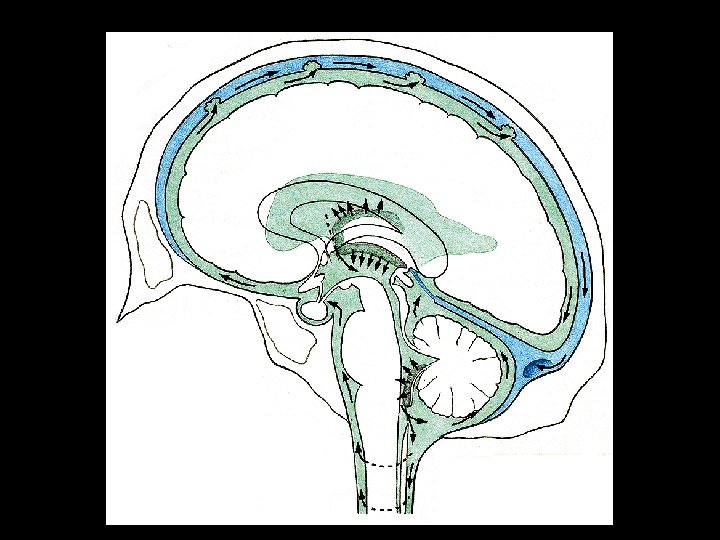

Liquor cerebrospinalis (CSF) Clear, colorless fluid, 150 m. L, secreted at the rate of 400 -500 m. L daily Produced by the choroid plexuses of ventricles Protects the brain, prevents the weight of the brain from compressing the nerves and vessels against the cranium. Circulation: Lateral ventricles – for. interventriculare – 3 rd ventricle – aquaqeductus cerebri – 4 th ventricle – median and lat. apertures – subarachnoid space – sinus durae matris

Hydrocephalus